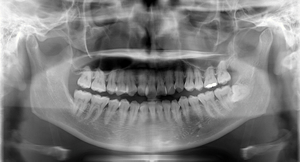

歯がある人

精密義歯装着5年後

顎の骨の高さが維持されています。

何年も義歯に問題を抱えて来院された方

大きく骨が吸収しています。これ以上吸収すれば、骨折の危険性もあります。